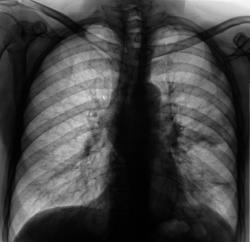

Рентгенограммы и их фрагменты.